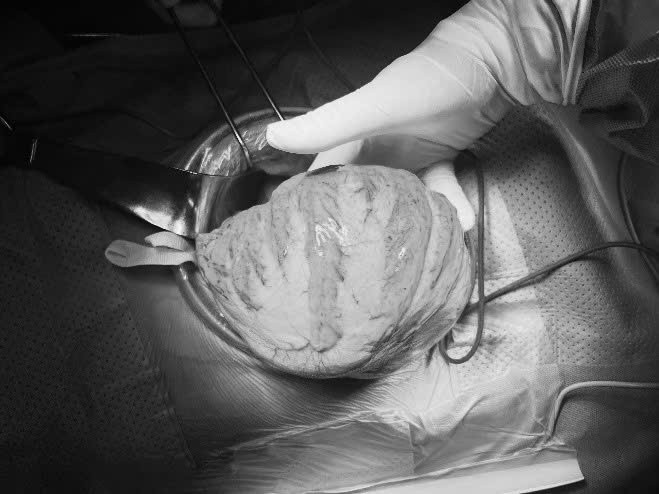

Bệnh nhân đã được bù dịch điện giải; nuôi dưỡng tĩnh mạch trước mổ. Trong mổ thấy toàn bộ khung đại tràng giãn lớn đường kính >10 cm; thành dày; trương lực có giảm. Khối phân kích thước khoảng 20 x 30 cm ở đại tràng sigma.

![]() |

| Ca phẫu thuật lấy khối phình cho bệnh nhân - Ảnh BVCC |